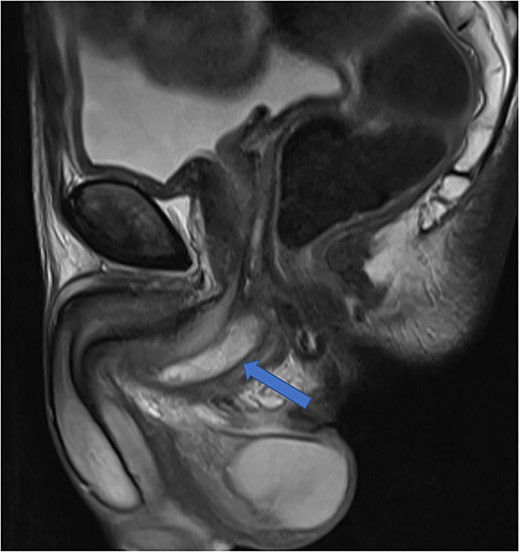

The diagnosis of an infected Cowper’s syringocele was made. The patient underwent ultrasound guided transperineal aspiration of the collection with an 8Fr needle, which drained 40 ml of the purulent material. There was no growth on the pus culture. He clinically improved, with significantly reduced swelling of the perineum and scrotum, and was discharged 48 h later, on oral antibiotics. Post-aspiration uroflowmetry determined a maximum flow rate of 20.8 ml/s. The patient was taught clean intermittent self-catheterisation due to post-void residuals of 300 ml. The patient’s perineal pain had much improved. Repeat MRI at 4 weeks showed a reduced but persistent perineal collection (Fig. 5). He is awaiting specialist review regarding potential further treatment in view of the residual collection.

Case 2: T2-weighted sagittal image showing a reduced perineal collection post-aspiration.